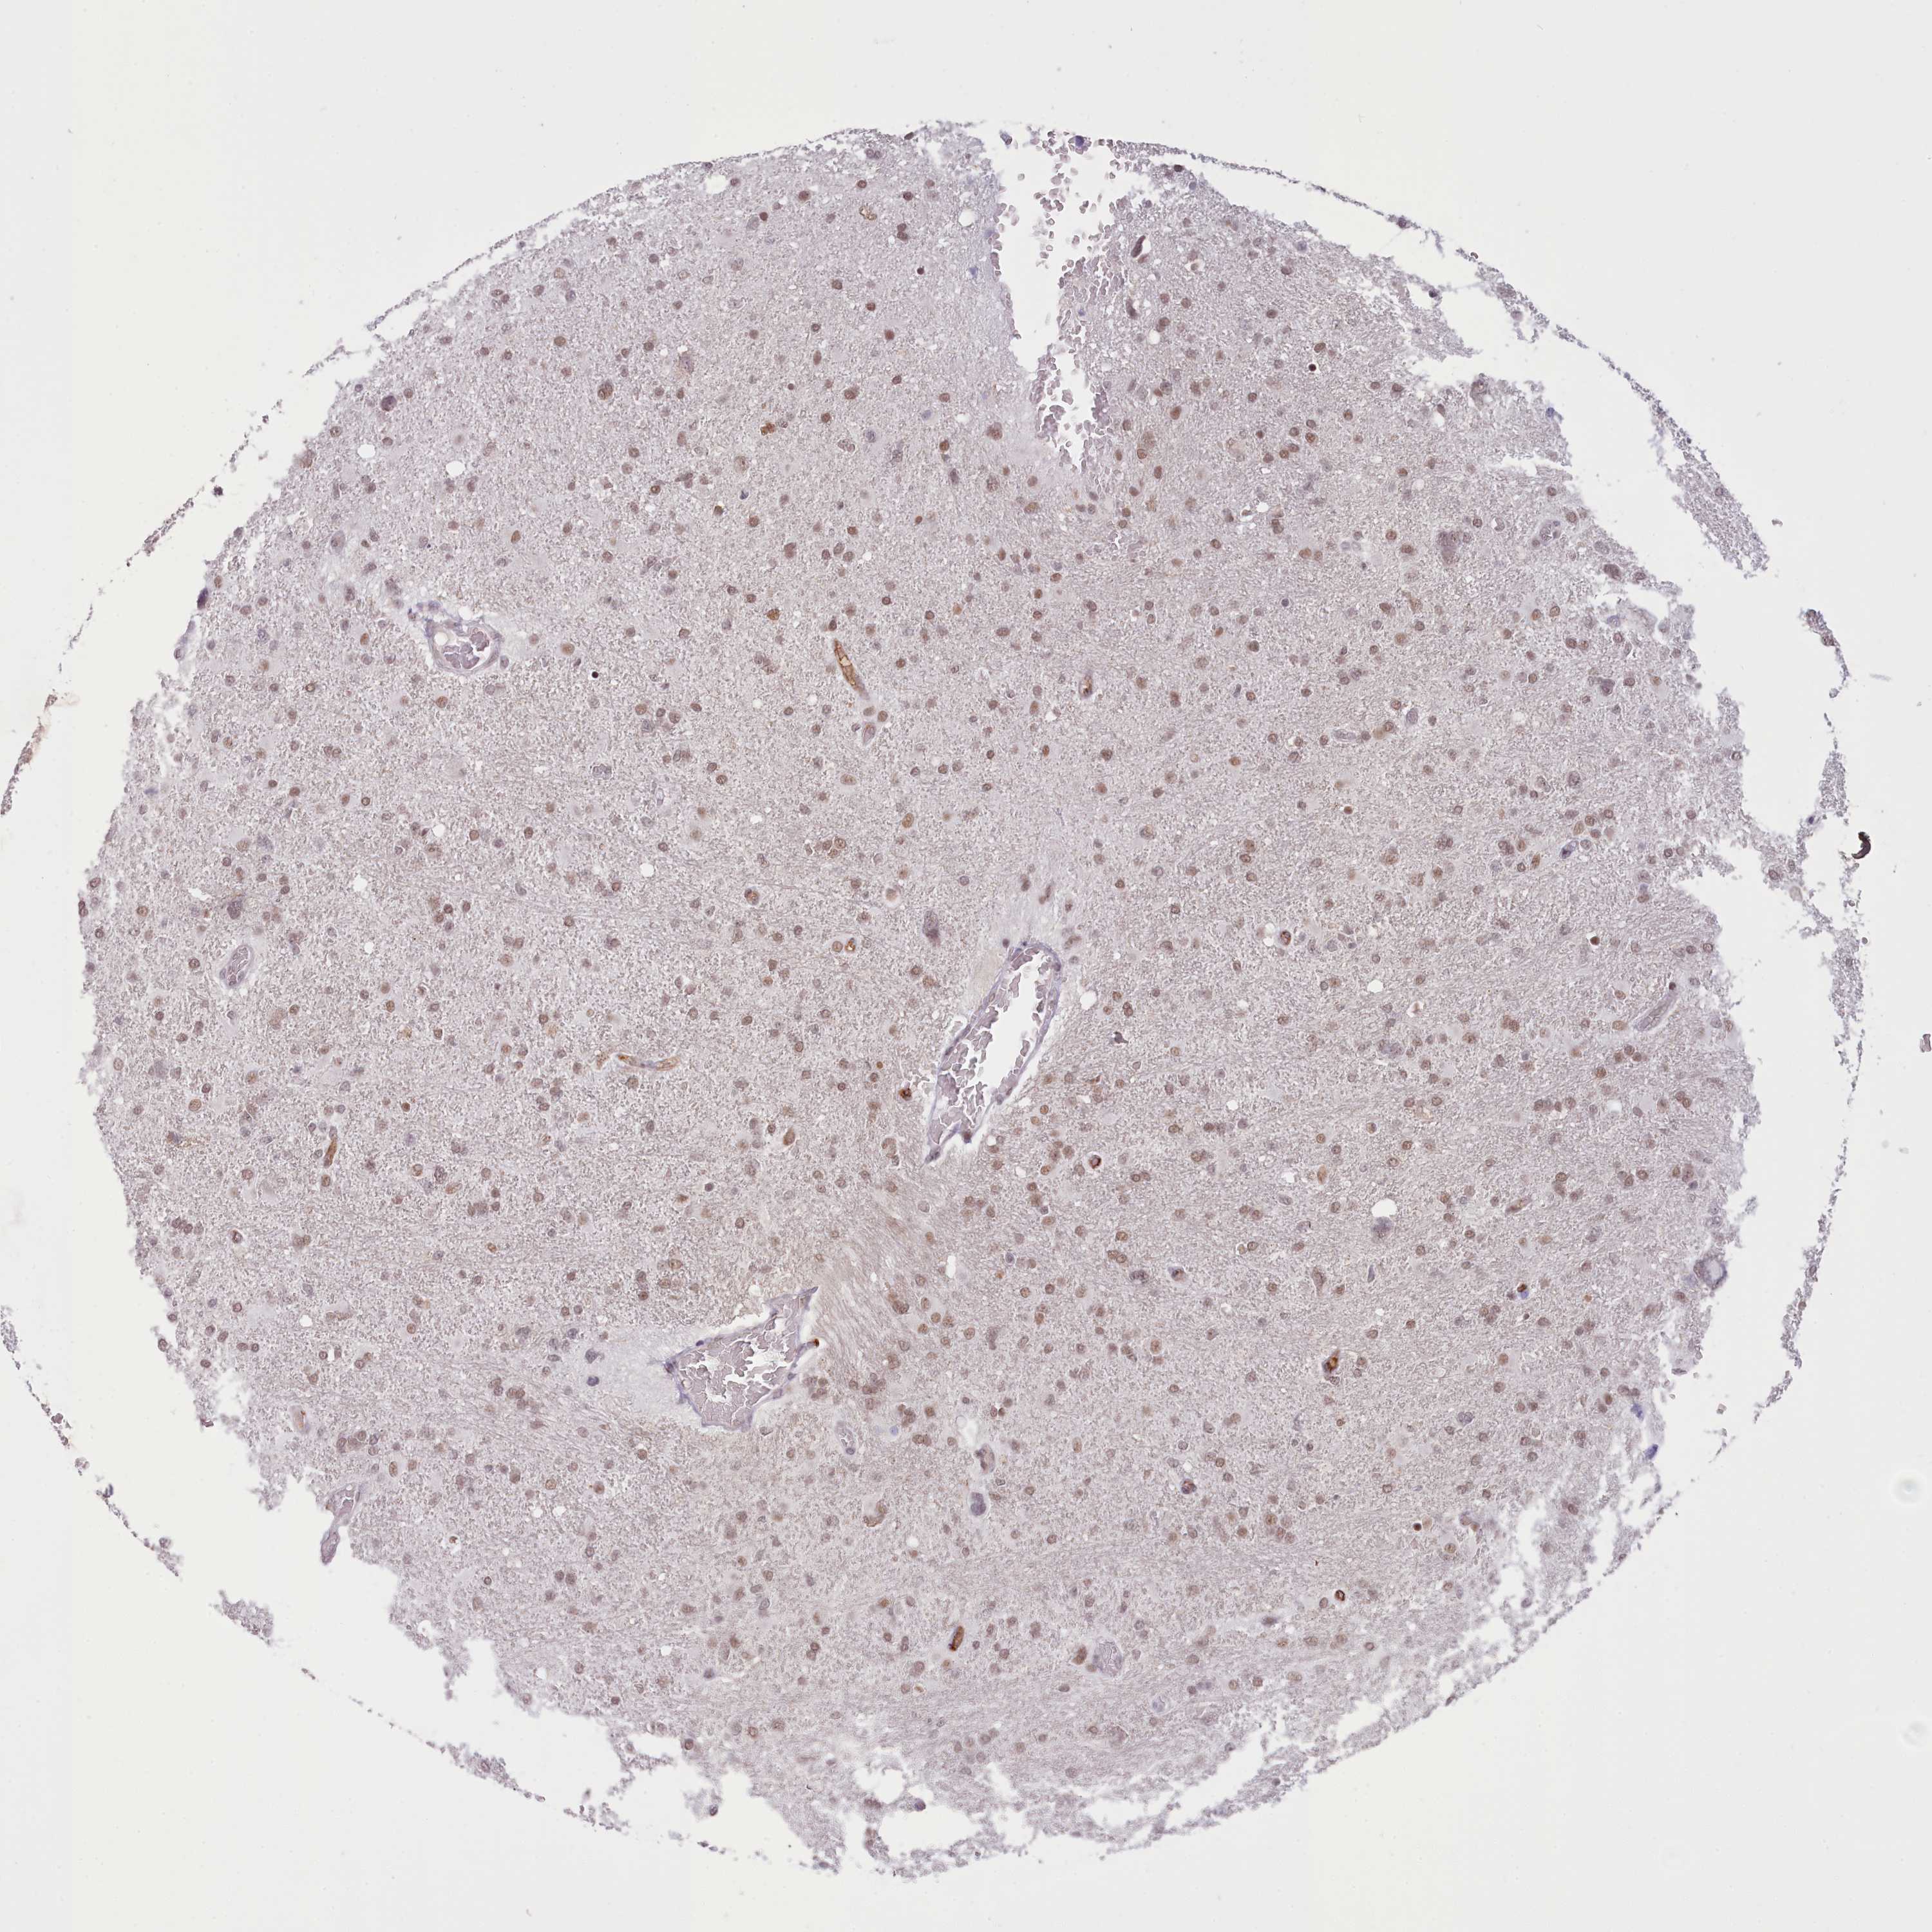

GLIOMA - Protein expressioni

A mouse-over function shows sample information and annotation data. Click on an image to view it in a full screen mode. Samples can be filtered based on level of antibody staining by selecting one or several of the following categories: high, medium, low and not detected. The assay and annotation is described here.

Note that samples used for immunohistochemistry by the Human Protein Atlas do not correspond to samples in the TCGA dataset.

Antibody stainingi

Antibody staining in the annotated cell types in the current human tissue is reported as not detected, low, medium, or high, based on conventional immunohistochemistry profiling in selected tissues. This score is based on the combination of the staining intensity and fraction of stained cells.

Each image is clickable and will lead to virtual microscopy that enables deeper exploration of all samples and also displays staining intensity scores, fraction scores and subcellular localization as well as patient and tissue information for each sample.

Antibody HPA048722

Staining

High

Medium

Low

Not detected

Intensity

Strong

Moderate

Weak

Negative

Quantity

>75%

75%-25%

<25%

None

Location

Nuclear

Cytoplasmic/membranous

Cytoplasmic/membranous,nuclear

Glioma, malignant, High grade

Glioma, malignant, Low grade